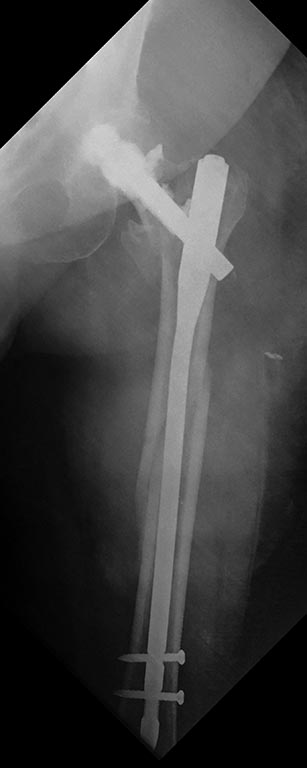

Закрытое штифтование с удлинением бесцементной ножки при переломах Vancouver B2/ B3 дает неожиданно для приверженцев традиционной догмы хорошие результаты.

Здесь первое наше наблюдение такого остеосинтеза с нестабильной ножкой. Прошло уже 6 лет - вот недавние снимки. Пациент не имеет жалоб, катается на коньках. Никакие дистальные винты не выдержали бы циклических нагрузок столько лет, если бы ножка оставалась нестабильной.

Как только увидел снимок, сразу промелькнула мысль - на старый гвоздь одеть новый ретроградный, именно это первым делом порекомендовал Шнеттлер. Отличные кейсы на этот счёт продемонстрировали Александр Николаевич и Алексей Юрьевич. По-моему, это очень даже reasonable вариант, учитывая аугментацию головки и остеопороз проксимального отдела.